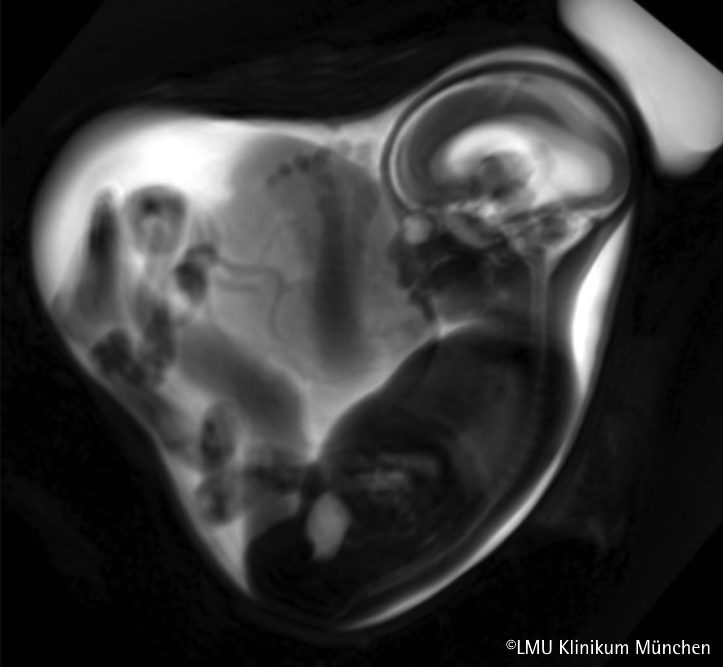

Titelbild: Die fetale MRT ist eine spezialisierte Bildgebungsmethode der pränatalen Diagnostik, die etwa ab der 18. Schwangerschaftswoche eingesetzt werden kann. Abb.: LMU Klinikum München

Die Forschenden um Prof. Dr. Sophia Stöcklein von der Klinik und Poliklinik für Radiologie des LMU Klinikums und Privat-Dozentin Dr. Anne Hilgendorff vom Zentrum für Comprehensive Developmental Care des LMU Klinikums und von Helmholtz Munich haben insgesamt 34 Schwangere respektive Feten mittels fetaler MRT untersucht. Die fetale MRT ist eine hochspezialisierte Untersuchungsmethode, die es ermöglicht, die Entwicklung fetaler Strukturen bereits vor Geburt detailliert zu untersuchen. Die Frauen hatten sich zu unterschiedlichen Zeitpunkten mit der Alpha-Variante des Corona-Virus infiziert, bestätigt durch PCR-Test. Die Lungen der Feten wurden mittels Magnetresonanz-Tomografie vermessen, das Lungenvolumen bestimmt und mit Feten aus einer sogenannten Referenzkohorte verglichen, bei denen keine Infektion während der Schwangerschaft stattgefunden hatte.